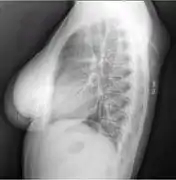

A physical exam is typically the easiest way to diagnose it. Rarely, a tissue biopsy or imaging may be required. The imaging modality of choice is magnetic resonance imaging (MRI) because it has superior sensitivity of distinguishing it from liposarcoma as well as mapping the surrounding anatomy.[22]

Lipomas are rarely life-threatening, and the common subcutaneous lipomas are not a serious condition. Lipomas growing in internal organs can be more dangerous; for example, lipomas in the gastrointestinal tract can cause bleeding, ulceration, and painful obstructions (so-called "malignant by location", despite being a benign growth histologically).[33][34] Malignant transformation of lipomas into liposarcomas is very rare, and most liposarcomas are not produced from pre-existing benign lesions.[28] A few cases of malignant transformation have been described for bone and kidney lipomas,[35][36] but it is possible that these few reported cases were well-differentiated liposarcomas in which the subtle malignant characteristics were missed when the tumor was first examined.[37] Deep lipomas have a greater tendency to recur than superficial lipomas because complete surgical removal of deep lipomas is not always possible.[37][38]

The presence of multiple lipomas, lipomatosis, is more commonly encountered in men. Some superficial lipomas can extend into deep fascia and may complicate excision. Liposarcoma is found in 1% of lipomas and is more likely to occur in lesions of the lower extremities, shoulders, and retroperitoneal areas. Other risk factors for liposarcoma include large size (>5 cm), associated with calcification, rapid growth, and/or invasion into nearby structures or through fascia into muscle tissue.[39]